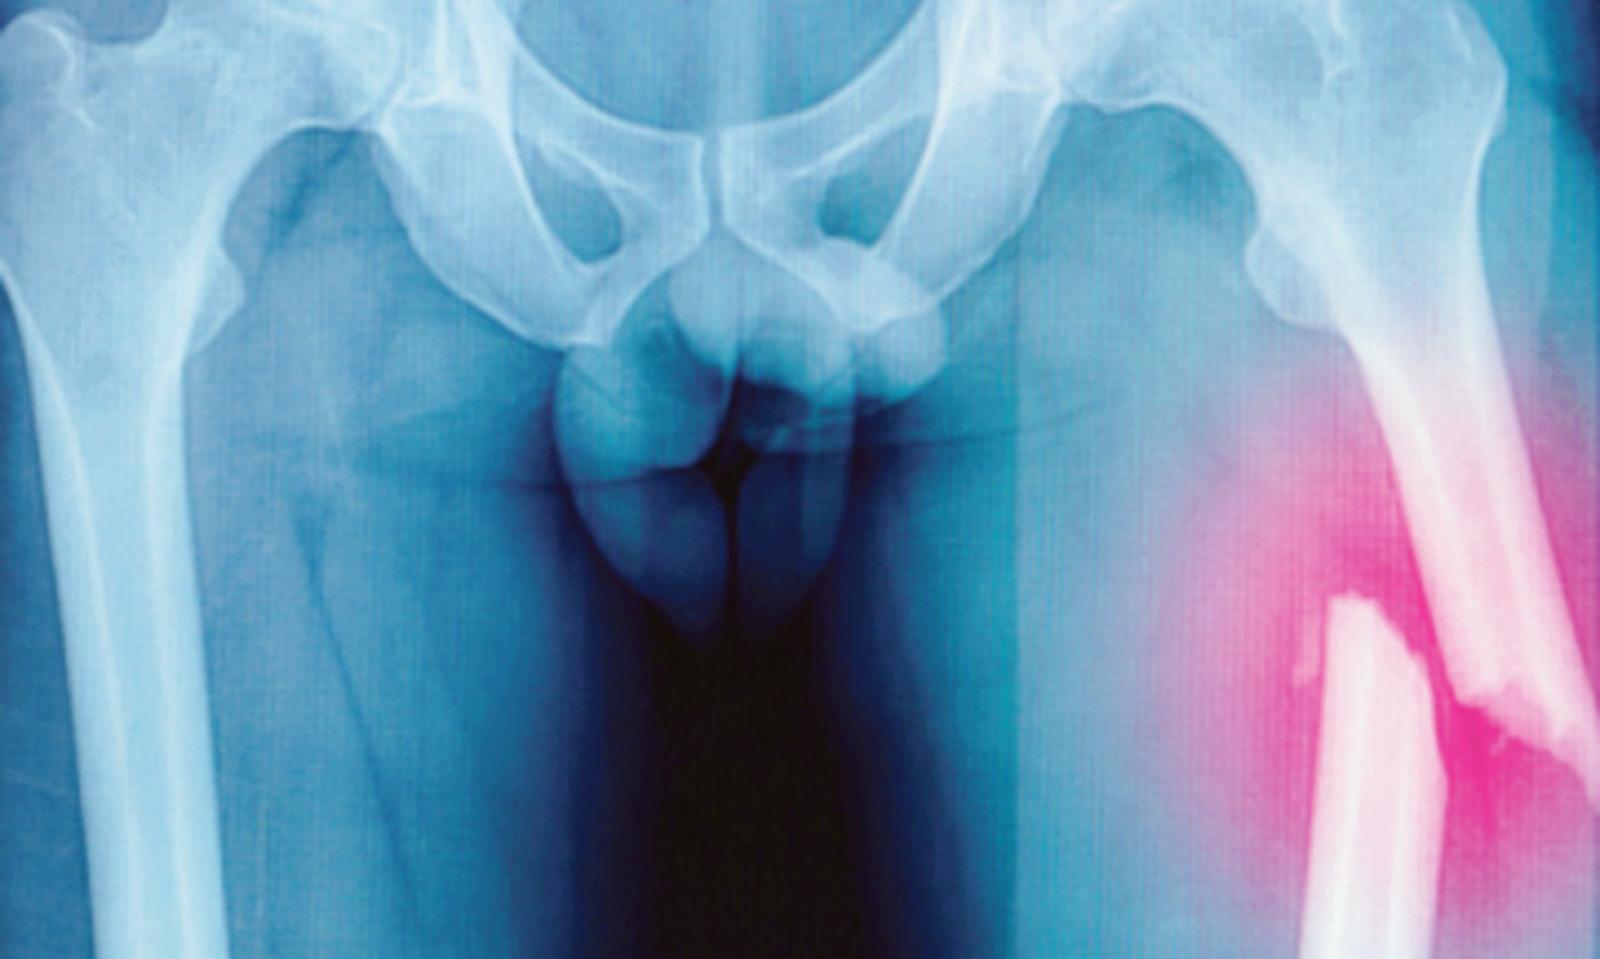

Quattro settimane in attesa di un’operazione per fratture riportate durante un incidente domestico. Il Comitato altopolesano del cittadini per il “San Luca” si muove per il caso del signor F. R. di Trecenta, “che in seguito a un incidente domestico è rimasto ricoverato dal 1° novembre nel reparto di ortopedia dell’ospedale di Rovigo per le fratture riportate in un incidente domestico. La frattura al femore sinistro richiede un intervento chirurgico”.

Un mese prima di essere operato, ma è lo stesso direttore generale Pietro Girardi a spiegare cosa è successo: “Purtroppo sono stati necessari degli esami aggiuntivi istologici che hanno rallentato le tempistiche. Infine c’è stata un’emergenza pediatrica. L’intervento è stato fissato per oggi. Sono casi straordinari perché le tempistiche per gli interventi ortopedici non sono queste”.

Il comitato rappresentato da Pietro Tosarello, tuttavia sottolinea: “Nel frattempo gli sono stati eseguiti accertamenti che non riguardano la frattura, sulla quale era comunque necessario intervenire, che non hanno portato ad alcun risultato. E poi continui rinvii dell'intervento. Ieri (il 27 novembre), per l'ennesima volta, ha atteso, a digiuno, per tutta la giornata, di essere operato. Nessun medico gli ha comunicato che, anche questa volta, non ci sarebbe stato l'intervento”.